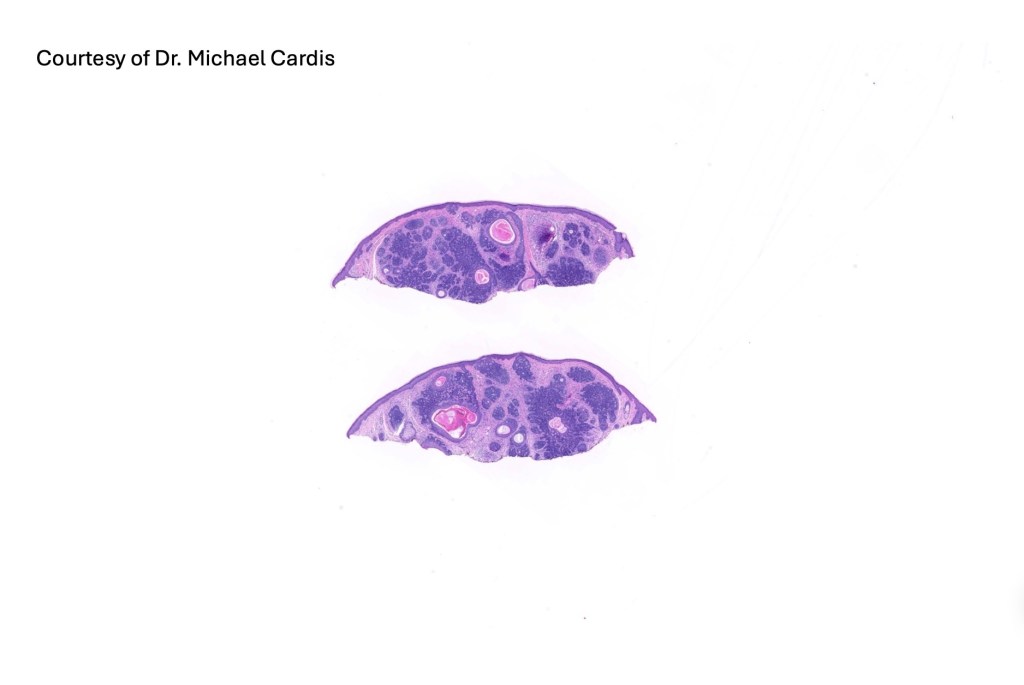

Trichoepithelioma is a hamartoma comprising a basaloid/germinative component and a prominent perifolliclular sheath proliferation. It may present as a solitary lesion or as multiple, familial lesions in multiple familial trichoepithelioma (which is probably a variant of Brook-Spiegler syndrome) & Brook-Spiegler syndrome.

•The classical appearance consists of keratocysts & lobules of basaloid cells

•Some tumors are devoid of keratocysts

•Perifollicular mesenchyme is always conspicuous and sometimes densely aggregated are seen indenting the baslaloid lobules (papillary mesenchymal bodies)

Trichoepithelioma should be distinguished from trichoblastoma since the latter is very rarely syndromic. Trichoepithelioma is largely a dermal tumor whereas trichoblastoma often extends from the dermis into subcutaneous fat or deeper in very large examples. Papillary mesenchymal bodies are much better formed and generally more obvious in trichoepithelioma. Trichoepithelioma must also be distinguished from basal cell carcinoma. Retraction artifact & stromal mucin are features of basal cell carcinoma and not trichoepithelioma. Papillary mesenchymal bodies are not seen in basal cell carcinoma.